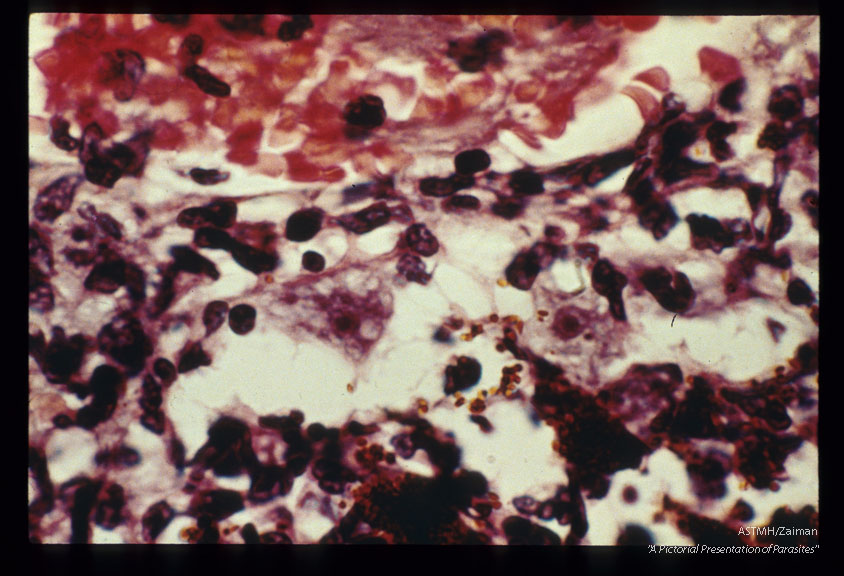

Fatal case with uveitis and meningoencephalitis. Trophozoite.

Acanthamoeba

Description: Fatal case with uveitis and meningoencephalitis. Trophozoite.